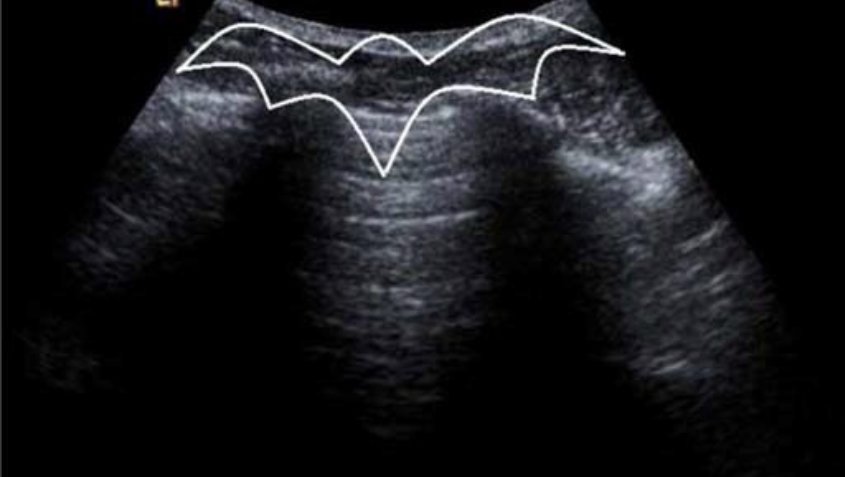

蝙蝠征

其中,蝙蝠翅膀为上下 2 根肋骨的横切面及其声影,蝙蝠体为肺实质